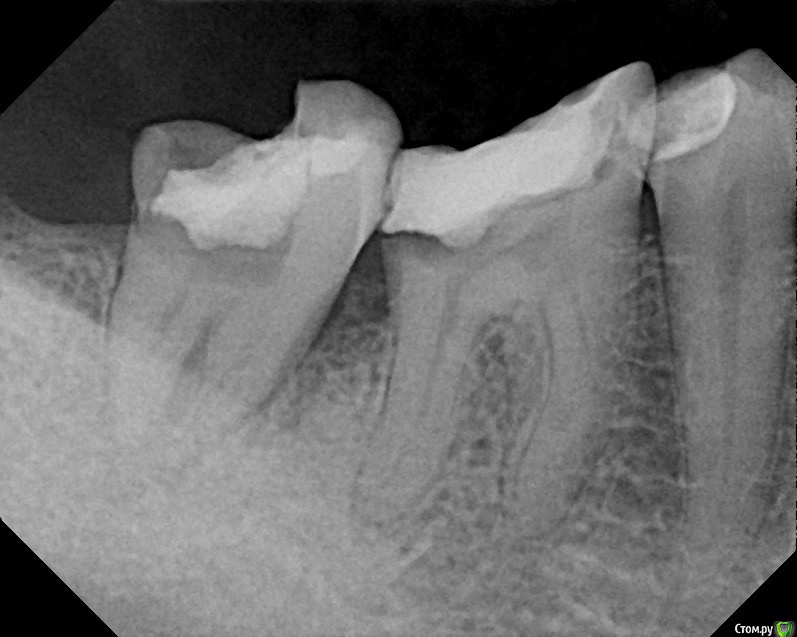

St616 Опубликовано 2 декабря, 2014 Поделиться Опубликовано 2 декабря, 2014 Добрый день ! Прошу вас посмотрите пломбировку каналов метапексомПосле пломбировки 2 дня сильная боль при нажатии и вообще.Сегодня пятый день, зуб поднывает и еще качается.Дело в том что у меня грудной ребенок, я его кормлю и поэтому не хотелось может более сильных, но не безопасных средств. Нервы удаляли с анастезией без лекарств. Тк был предложен только мышьяк. А у меня ребенок га гв. Пломбировка каналов и окончатильная очистка уже через 7 дней в другой клинике, хотели гуттаперчей. Но тк зуб качался сделали метапексом, врач вроде хоть и молодой но оч грамотный. Меня волнует небольшое темное пятно в одном канале под пломбой, это что воздух там? Не из ха этого ди боль сохраняется, сейчас уже небольшая. Воач по снимку сказал, что всё хорошо, а боль из за того что метапекс вышел за пределы. Фото до и после Ссылка на комментарий

anvladd Опубликовано 2 декабря, 2014 Поделиться Опубликовано 2 декабря, 2014 на счет темного пятна не беспокойтесь,а боль из за того что материал вышел за верхушку,должен рассосаться. Боль совсем не утихает? Ссылка на комментарий